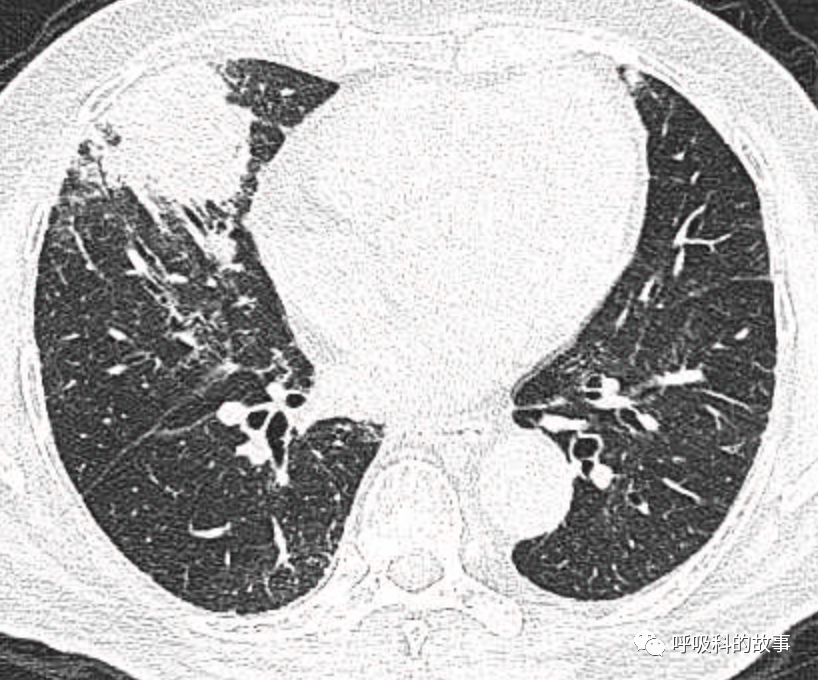

1个月前,我们收治了一个80多岁的男性患者,两肺多发结节和肿块,锁骨上淋巴结也触及肿大,在接诊时我们就预感不妙,患者很可能是患上了肺癌。后来经过穿刺后明确为大细胞神经内分泌癌,CT如下。

图1-11:该患者各个角度的影像图像

(上下滑动查看全部图片)